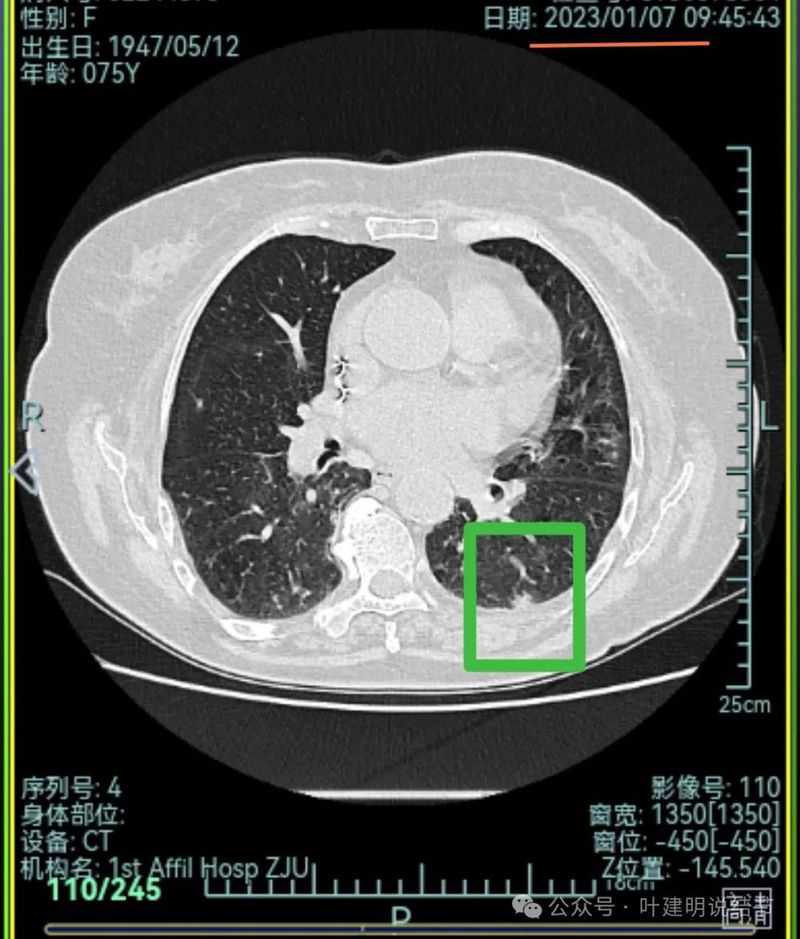

再来看2024年9月时的关键影像:

右上后段灶病灶不单没有好转,灶内密度是有增加进展的!

现在的影像考虑:

不单是右中叶以及右下叶的病灶吸收消失了,两肺其他病灶也基本上都不见了,唯独右上后段的病灶仍在而且有进展!再加上此灶原来单看也像恶性的,所以这位结友是感染与肿瘤并存,右上病灶基本上肯定是恶性的,而且是浸润性腺癌。

主病灶连续层面展示分析:

病灶出现,磨玻璃密度,轮廓与边界均清楚,灶内密度稍不均。

有明显血管进入,表面分叶,边缘不平,整体轮廓清。

边缘毛刺、表面不平、灶内偏实性成分、分叶明显,整体轮廓与瘤肺边界较为清楚。

灶内细支气管扩张、边缘毛刺较为锐利、有明显磨玻璃成分,磨玻璃成分的瘤肺边界清楚,病灶分叶明显。

灶内密度杂乱不均,内有小空泡征,表面不平。

灶内血管增粗穿行、磨玻璃成分明显,轮廓较清。

血管进入,磨玻璃成分,支气管扩张,边缘不平。

典型混合密度病灶,中间部分密度高偏实性,外围部分磨玻璃密度,两者之间交错存在,说明偏实性部分有侵袭性。磨玻璃成分与正常肺组织之间界限清楚,表面分叶,部分边缘毛刺,整体轮廓清。是非常符合恶性的影像表现。

灶内磨玻璃成分明显,并有异常增粗血管僵硬穿行于病灶内,支气管有扩张通气征,瘤肺边界清楚,实性成分明显。